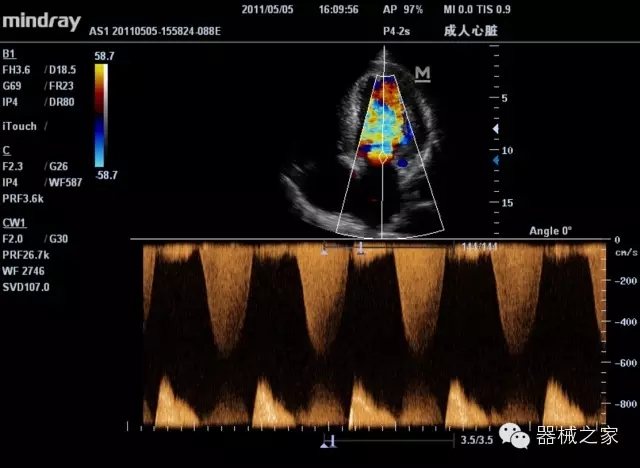

臨床圖片賞析

產(chǎn)品特點